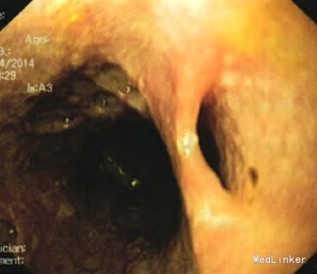

入院后查体:神志清楚,消瘦貌,中度营养不良。双肺听诊呼吸音粗,未闻及干湿性啰音。心律齐,各瓣膜听诊区未闻及病理性杂音。腹平,无腹壁静脉曲张,未见肠型、蠕动波。腹软,剑突下轻压痛,无反跳痛,无肌卫,移动性浊音阴性,肠鸣音约4次/min。 入院后行胃镜检查示食管中下段散在数条沿食管纵轴向下延伸的条索状裂陷或口疮样溃疡灶,部分深潜呈窦道样改变(见图1~2)。 病理报告单:(食道)鳞形上皮黏膜急慢性炎,见部分坏死、肉芽组织,H.pylori(-)。 肠镜及全消化道造影检查未见明显器质性疾病。 全胸片示:右侧胸腔积液,右上肺斑片状及纤维索条状状影。

入院后初步诊断为食管结核,予以抗痨治疗后效果欠佳,后经全院病例讨论考虑食管Crohn病的可能性较大,加用强的松40mg qd,美莎拉嗪0.75g bid治疗一周后,临床症状明显缓解,故诊断为:1.食管Crohn病,2.两肺陈旧性结核。